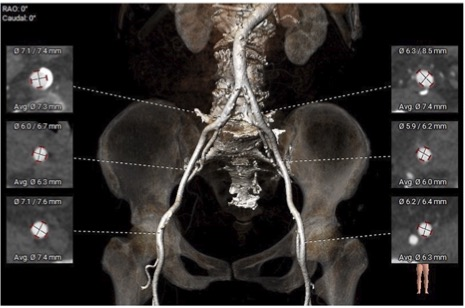

腹主-双侧髂总动脉未见明显钙化,股-髂动脉走行流畅、内径可,分叉高。

股-髂动脉走行、内径可